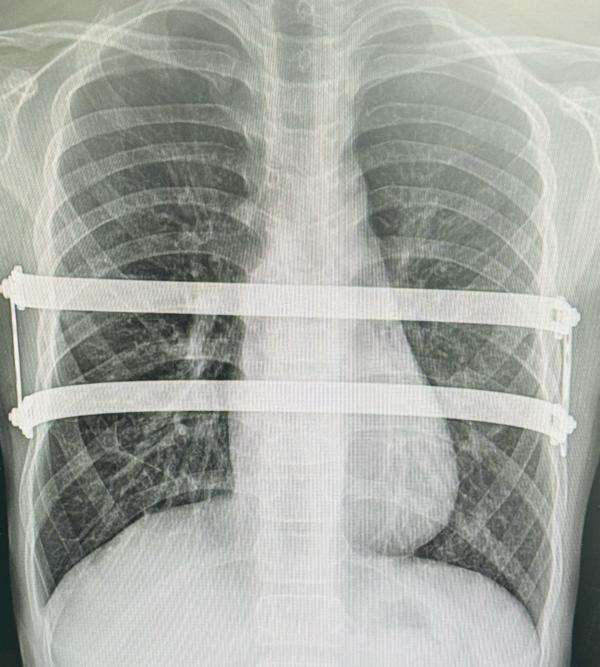

The modified NUSS procedure is a minimally invasiv...